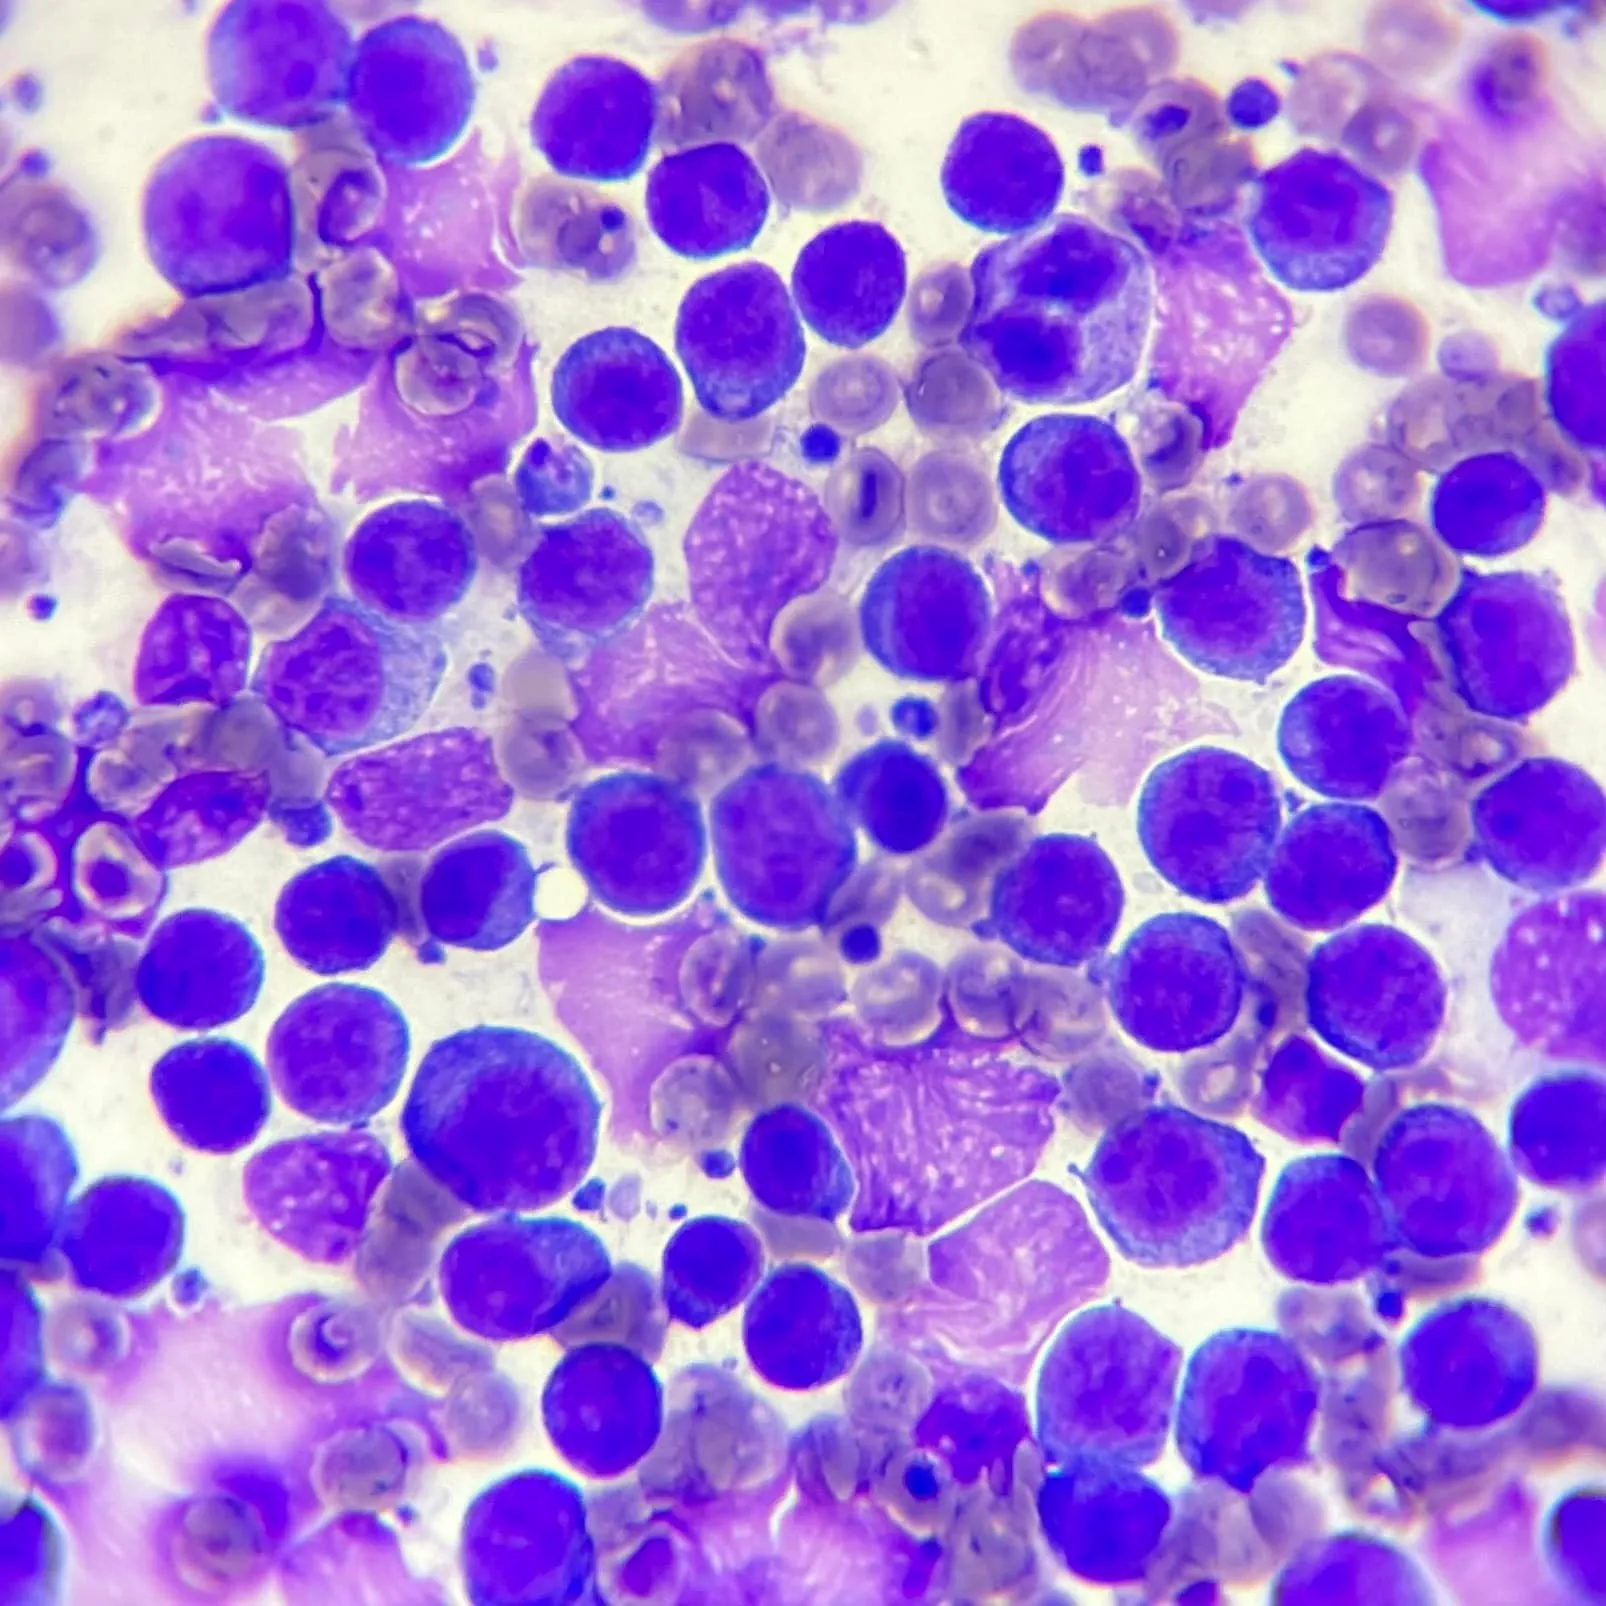

針對腫大的淋巴結、團塊,或體內病灶進行超音波導引針對腹腔腫塊或消化道壁採樣都可以確診。當然在細胞抹片的判讀上,會需要一定的經驗,且對抹片品質與採樣技巧上有一定的要求。

針對腫大的淋巴結、團塊,或體內病灶進行超音波導引針對腹腔腫塊或消化道壁採樣都可以確診。當然在細胞抹片的判讀上,會需要一定的經驗,且對抹片品質與採樣技巧上有一定的要求。